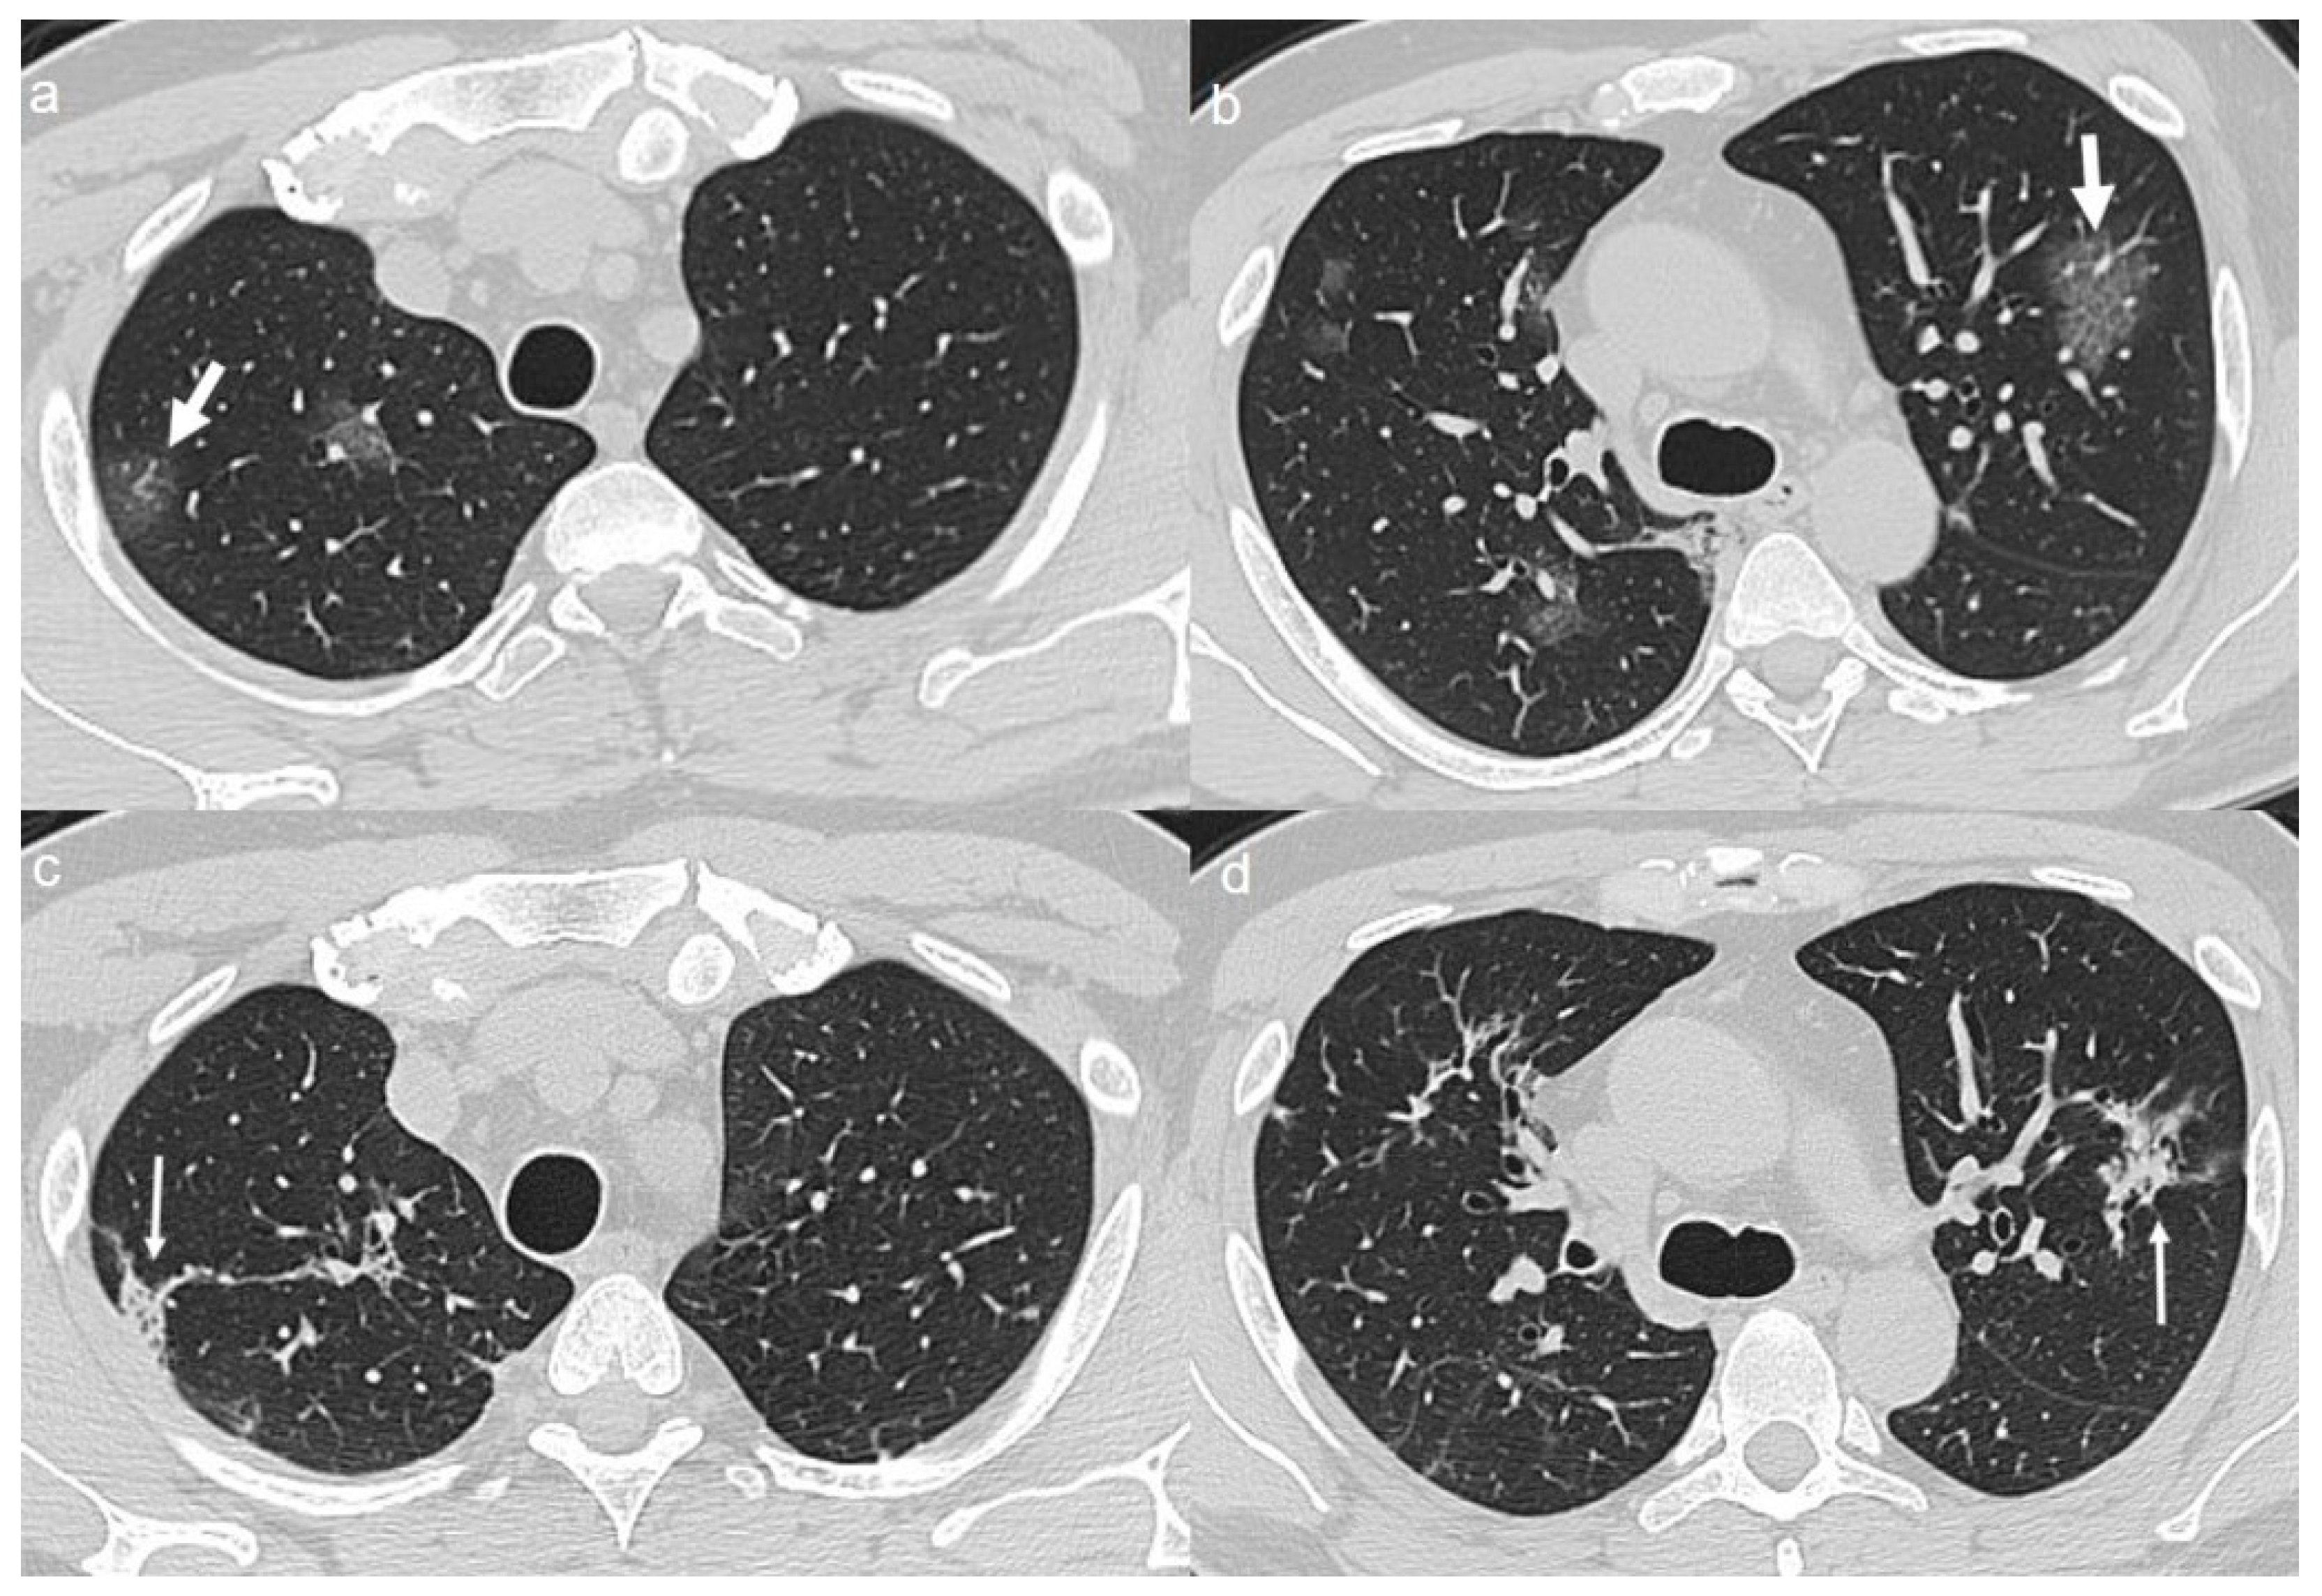

On admission, chest CT showed patchy areas of GGO with in upper lobes (Figure 4a,b), in the middle and left lower lobe (Figure 5a,b).

(a,b) CT shows patchy areas of GGO with in the upper lobes (arrows). (c,d) CT after 4 months from the onset of symptoms shows bilateral persistence of fibrotic stripes in upper lobes (thin arrows).

(a,b) CT shows patchy areas of GGO in the middle lobe (arrow in a) and in the left lower lobe (arrow in b). (c,d) CT after 4 months from the onset of symptoms shows bilateral persistence of fibrotic stripes in middle lobe (thin arrow in c) and in left lower lobe (thin arrows in d).